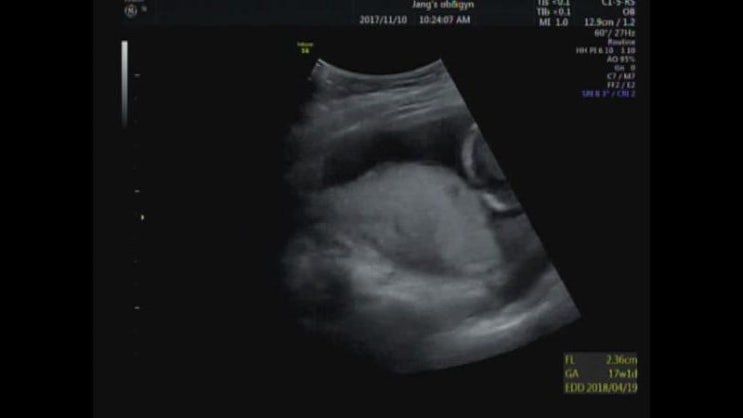

[ReRe]16w2d 드디어 나온 성별!!

성별..그게머하고ㅋㅋ16주가 되기만을 얼마나 기다렸던가!!! 두근두근 설레는 마음으로 병원에 갔지요잉? ...